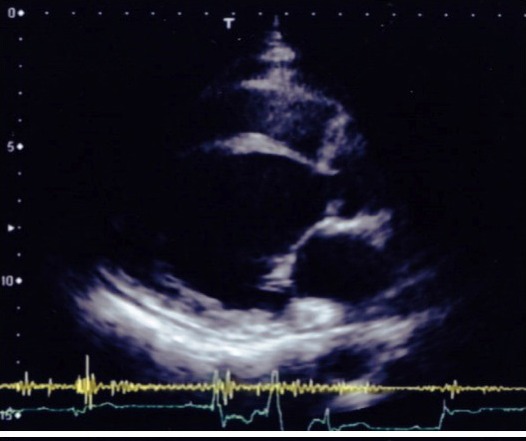

経胸壁心エコー検査(図2)では、傍胸骨左室長軸断面で左室中隔基部の菲薄化を認めた。これらの所見から刺激伝道系の器質的障害があると考えられ、徐脈性不整脈によるアダムストークス発作が生じている可能性を考え精査目的で入院となった。入院後、失神時の心電図モニターで発作性房室ブロックによる約15秒のRR延長(図3)を認めたため緊急一時ペーシングを施行した。採血では炎症反応やACE活性の上昇はなかったが、眼科よりぶどう膜炎の既往の指摘があり、胸部CTでは傍大動脈リンパ節腫脹があった。造影MRIでは左室中隔に遅延造影を認めた。臨床的には心サルコイドーシスであると判断し、プレドニン30mgの導入を開始した。その後も発作性房室ブロックを繰り返し生じており、恒久型ペースメーカーの植え込みを施行した。

図2

入院時の心電図は完全右脚ブロックと1度房室ブロックの合併であり、電気軸が正常であることから左脚ヘミブロックとは診断できない。3束ブロックや交代性脚ブロックがないことから完全房室ブロックへの進展のリスク予測は困難であったが、意識消失発作を呈していることから発作性ブロックによるアダムストークス発作を生じている可能性があると判断した。また、心エコー検査で心室中隔基部の壁菲薄化と壁運動低下があることから房室伝導にHis束以下の器質的障害が及んでいる可能性があると考えた。入院中に発作性ブロックが生じ意識消失したが、幸いなことにTorsades de pointesなどをきたさず、直ちに一時ペーシングを施行した。このような症例で意識消失の既往があれば緊急入院と一時ペーシングの留置が安全である。本症例では心筋生検は施行されておらず心筋にサルコイド結節の証明ができていないが、臨床的には心サルコイドーシスによる発作性ブロックであると診断し、ステロイドを導入し漸減した。現在15mgの維持療法中である。